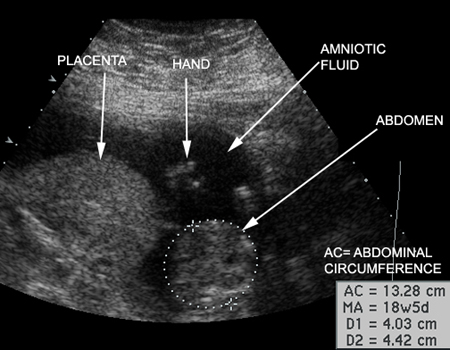

Items Measured by Ultrasound |

Measurements |